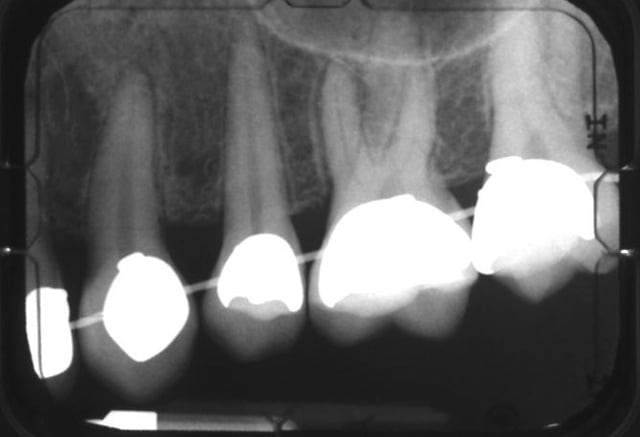

bon les gars, si on part du principe qu'il faut que je m'inquiète pour ces dents-là, alors il faut que j'en fasse autant pour ces 16 et 26, avec leurs épaississements ligamentaires...

et on est pas sorti de l'auberge...

16 dd4xmj - Eugenol

26 djjirf - Eugenol

Fais gaffe quand meme au risque de fenestration, doc . Ton image radio claire a l'apex montre quand meme un risque possible. Ne presse pas ton ortho a finir trop vite.....

> Fais gaffe quand meme au risque de fenestration, doc . Ton image radio claire a

> l'apex montre quand meme un risque possible. Ne presse pas ton ortho a finir

> trop vite.....